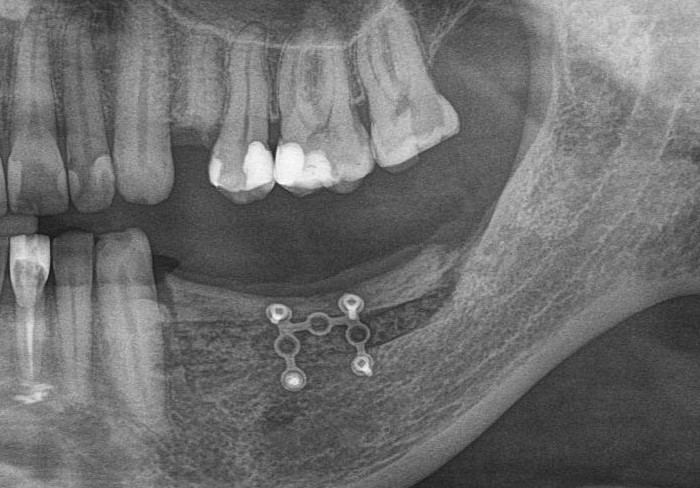

у меня появились серьезные сомнения, смогу ли я выполнить своё обещание. Вот только не спрашивай меня «Вот чо, сложно было по КЛКТ посмотреть?». Я же не спрашиваю тебя, где ты был в 2013 году, и сделал ли ты домашку. Но, в целом, план операции у нас не поменялся. Как и было оговорено, мы проведем остеопластику с одновременной имплантацией в боковом участке нижней челюсти справа.

Кстати, обрати внимание на ширину альвеолярного гребня (левая картинка). Она чуть меньше 3 мм. Это объясняет, почему я засомневался в возможности установки имплантатов одновременно с остеопластикой. Понятно и без КЛКТ.

Возвращаемся к основной операционной области. Еще раз посмотрим на альвеолярный гребень, поофигеваем от его ширины и моих грандиозных планов: